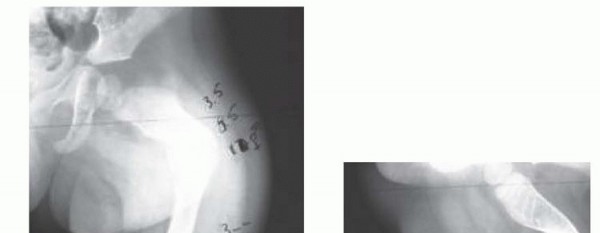

Coxa Vara

## If true coxa vara is present, it should be corrected at the same setting by combining this femoral nail

technique with the valgus osteotomy described by Fassier et al9 ( TECH FIG 4). Coxa vara can develop spontaneously, with or without weight bearing, or following osteotomy and intramedullary nailing.

## TECH FIG 4 • A. A 2½ year-old boy with OI who developed progressive painful right coxa vara with walking.

B. Age 3 developing coxa vara on left with progression in right hip. C. Age 3 bilateral valgus osteotomies. Note valgus correction and alignment of lateral cortex of the proximal segment with right femoral shaft. D. Distal femoral osteotomy to correct associated diaphyseal varus. E. At 13-month follow-up, maintenance of correction is demonstrated. The femoral head is growing away from the wires, and varus may recur.